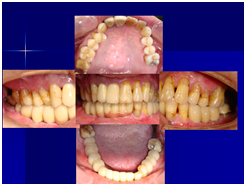

患者的原始片 91/06/13

患者陳先生於91/06/03初診,為一個牙周病患者,合併有右下缺牙。經過保守性牙周處理後,於91/08/14放置右下三顆植體。

完成後大約半年至一年進行一次例行性追蹤檢查,並無特別問題。以下為96/08/13時的追蹤小片,可以見到當時三顆植體的骨高度並無顯著變化。但右下第一小臼齒此時發現有搖動度增加的情形,當時對該顆牙做了咬合調整,降低咬合功能負荷,希望能有所改善。